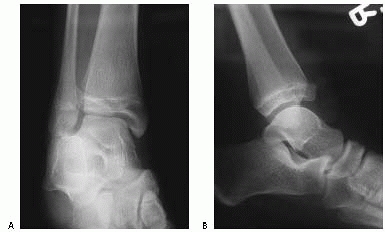

![]() |

FIGURE 26-10 A. Anteroposterior radiograph of Salter Harris type III/juvenile Tillaux Fracture. B. Lateral radiograph of Salter Harris type III/juvenile Tillaux Fracture.

|

III fracture involving the anterolateral distal tibia. The portion of

the physis not involved in the fracture is closed (Fig. 26-10).